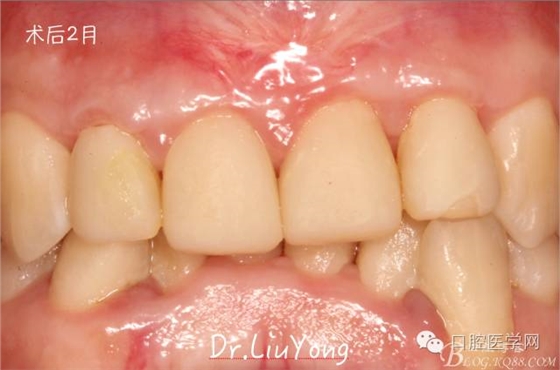

膜齦手術(shù)后2月復(fù)查,可以明顯觀察到,B12之間的牙齦乳頭明顯高度增加,黑三角得到很大改善,如下圖: